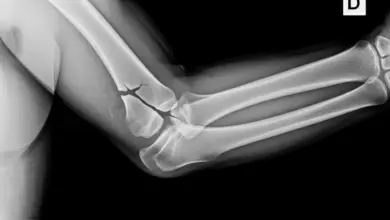

- A radiografia pode mostrar um pequeno fragmento ósseo avulsionado no olécrano, sinal indireto de ruptura.

O diagnóstico começa no exame clínico. O médico especialista em patologias do ombro avalia o mecanismo da lesão, inspeciona o edema e hematomas, palpa a inserção do tendão e testa força de extensão do cotovelo.

A suspeita de ruptura do tendão distal do tríceps aumenta quando há perda clara de força e dor localizada no olécrano.